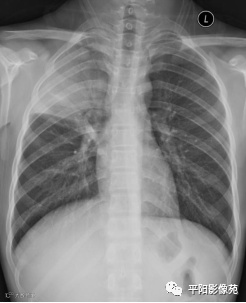

入院X线片:

影像特征:X线片右肺中上野片状高密度影,下缘以叶间裂为界,上缘及外侧缘模糊;CT位于右肺上叶后段,呈片状实变影,内见支气管影,边缘模糊。

影像诊断:右肺上叶大叶性肺炎。